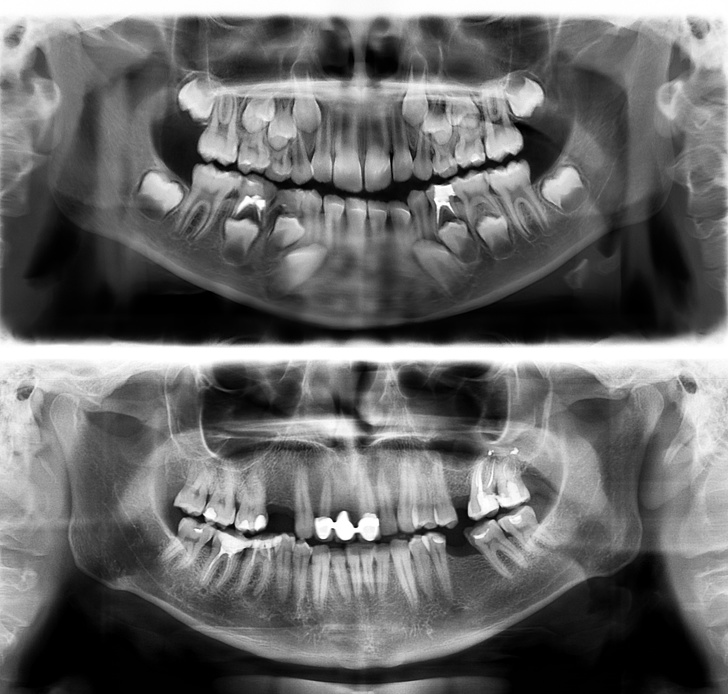

18. Так виглядають зуби людини у 7 (вгорі) і в 30 років